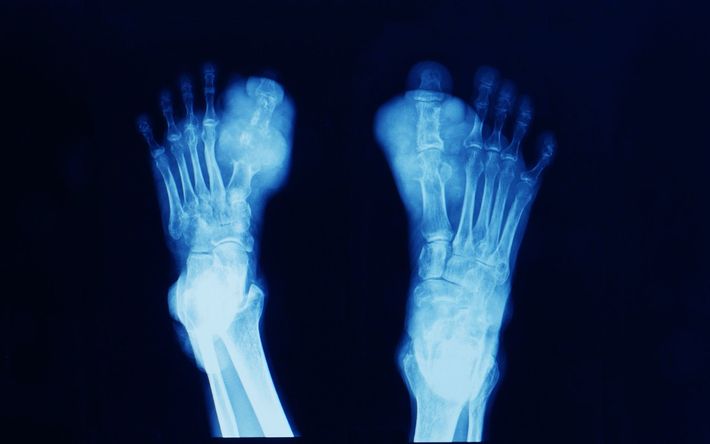

articolazioni metatarso-falangea, caviglia, ginocchio, gomito e polso. Quando si verifica, l'attacco è accompagnato da un dolore molto intenso, che ha un carattere urente e debilitante, e la sua durata può oscillare tra i 5 e i 10 giorni. È importante notare che questi episodi tendono a ripetersi nel tempo, con la caratteristica che gli attacchi diventano progressivamente più prolungati e i periodi di remissione si accorciano sempre di più, rendendo la gestione della condizione sempre più complessa e sfidante per i pazienti.